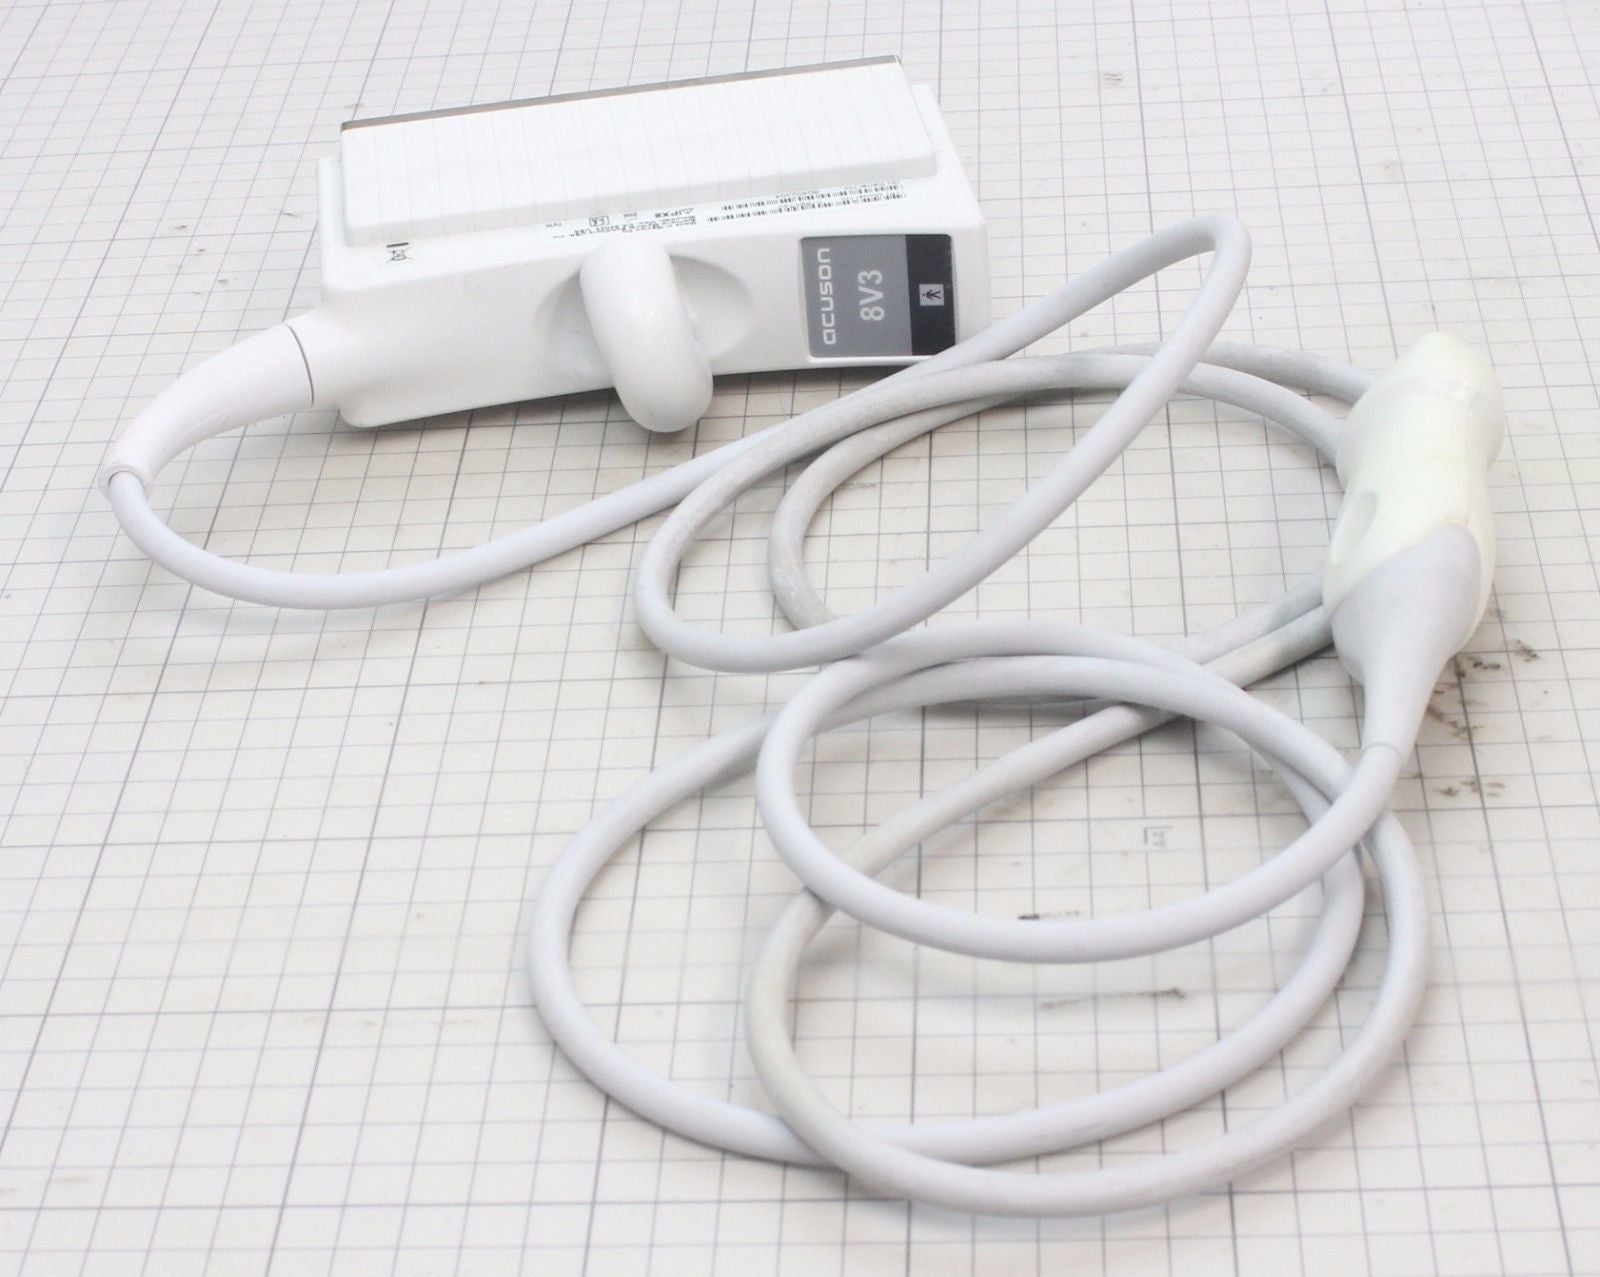

Acuson Probes

DIAGNOSTIC ULTRASOUND MACHINES FOR SALE

Acuson Linear Ultrasound Probe 7L3 08267217

Sale price$ 3,837.58